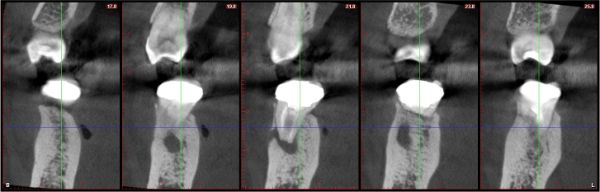

電腦斷層確認根尖病變